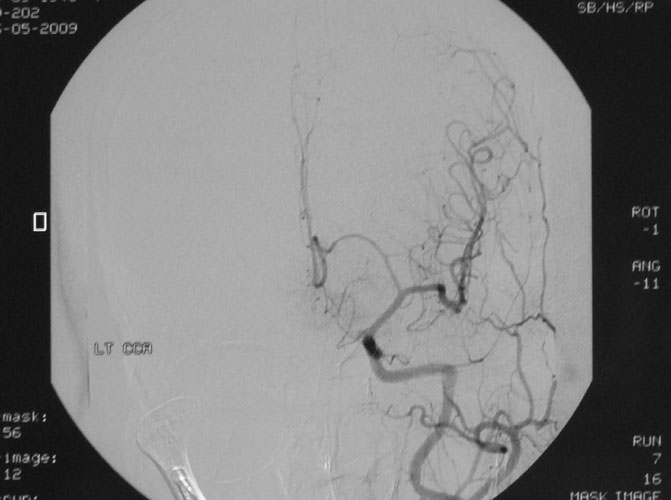

Arteriovenous malformations

Arteriovenous malformations of the brain are abnormal bunch of blood vessels that can rupture causing bleeding, or may cause seizures. Brain imaging (CT, MRI) is required for early diagnosis, while definitive treatment is carried out after cerebral angiography. Treatment implies craniotomy and excision of the AVM, which can be done safely in majority of the cases. Embolisation and radiosurgery are acceptable substitutes, but carry risk of further bleeding.